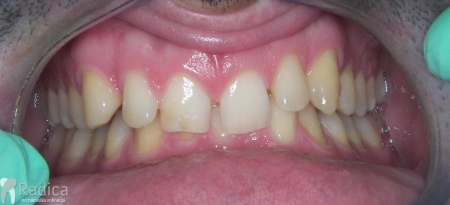

Slučaj 1: ispravljanje otvorenog zagriza i kompresije Invisalign full terapijom

Slučaj 2: ispravljanje kompresije Invisalign full terapijom- u ovom slučaju je izvađen jedan donji sjekutić

Slučaj 3: ispravljanje kompresije Invisalign full terapijom

Slučaj 4: ispravljanje kompresije Invisalign full terapijom

Slučaj 5: ispravljanje kompresije i križnog zagriza Invisalign full terapijom

Slučaj 6: ispravljanje kompresije i dubokog zagriza Invisalign full terapijom

Slučaj 7: ortodontska predprotetska terapija Invisalign full